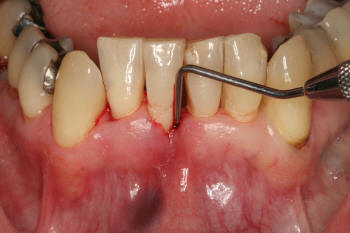

Realizar el

sondaje periodontal para identificar bolsas

sangrantes |